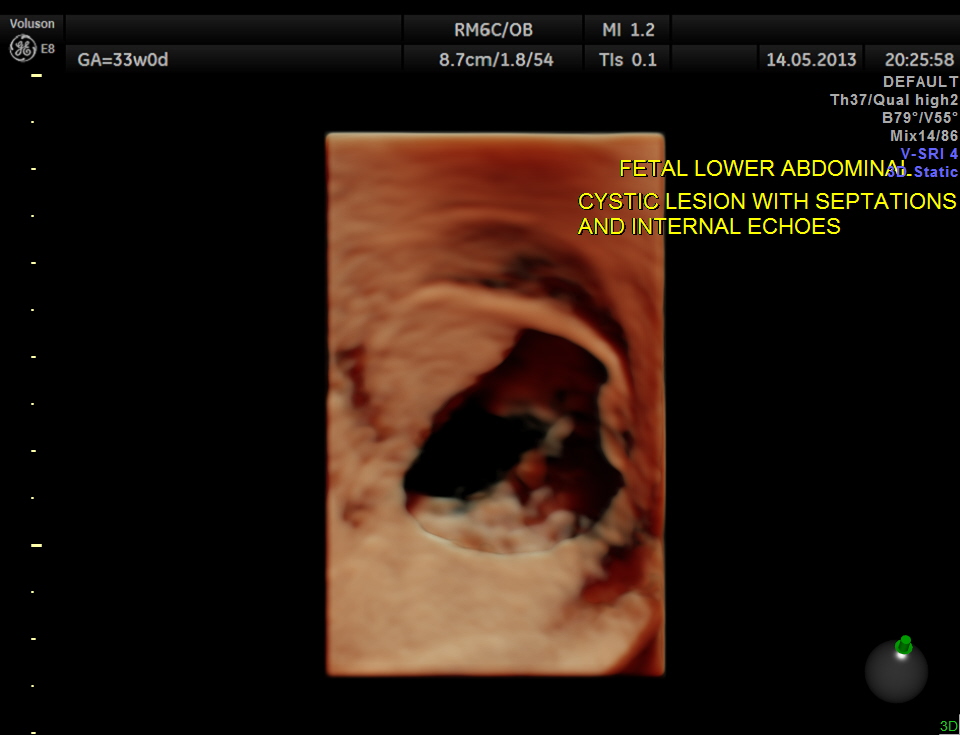

The lower abdomen showed a predominantly cystic mass with septations and internal echoes .

This was distinct from the urinary bladder and the kidneys. Both the kidneys showed mild pelviectasis.

The diagnosis offered was probable ovarian cyst with a D.D. of mesenteric cyst